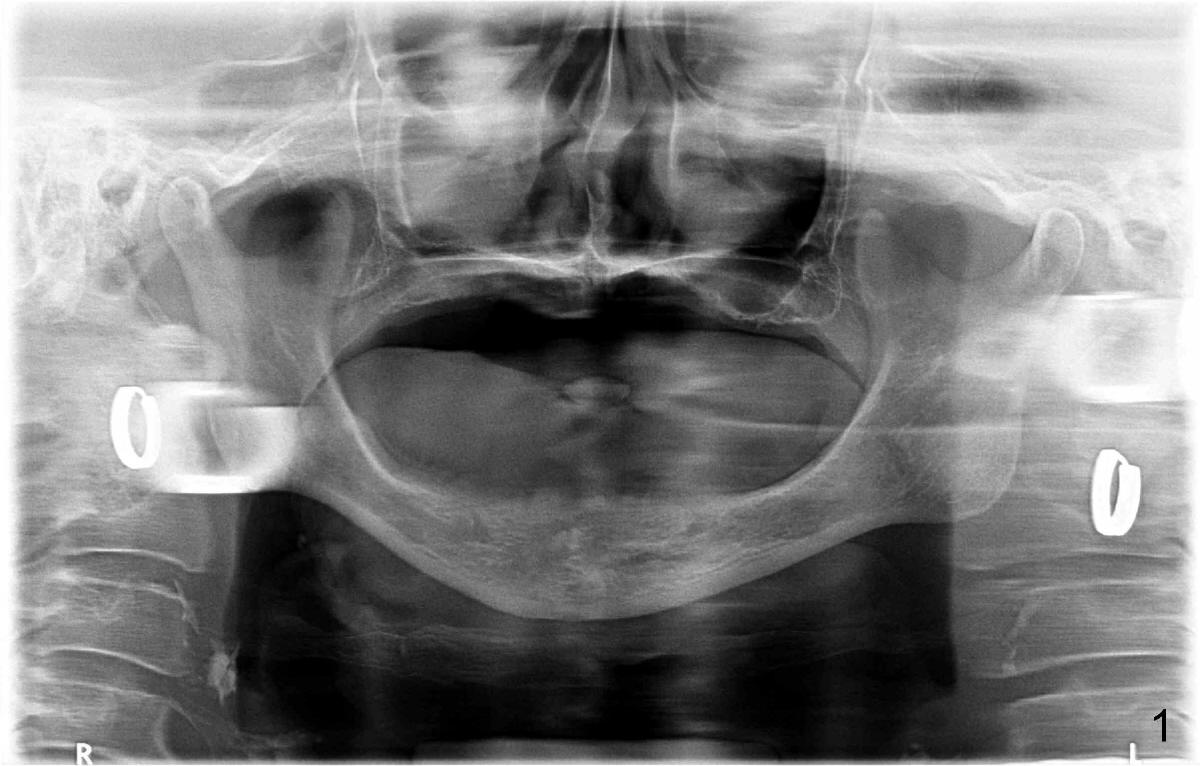

Here is another case: female, 68yrs, two implants supported overdenture, panorex was preop (Fig.1), pa with two implants was taken one week after implant insertion (Fig.2), another pa with some shadow was taken one month after surgery (Fig.3). Now presented fistula on the alveolar ridge. I have not idea what is going on? Do you have any idea/what causes it?  It happened couple cases already.  I handled these kinds of cases: take out implants, wait for healing and place implants again.

Robert: After reviewing X-ray, my impression is that the implant with radiolucency needs to be removed, the osteotomy thoroughly debrided and a larger implant placed immediately.  In addition, place one or two regular implants next to the infected implant.  Bury implant(s) if primary stability is not high.  The possible reason of the failure is overloading.  Did you load these two implants immediately?  Did you soft reline the denture immediately or relieve the denture tissue side enough?  Take CT before surgery. Thanks.

Bob: Thanks for nice presentation with attachment.  You asked a good question.  It appears that the radiolucency does not decrease as compared to 1 month follow up.  Even though the clinical sign improves, the right implant will be fibrointegrated at the best.  If I were you, I would open up soon.  If bone is healthy around the implant, remove granulation tissue if present.  If it looks bad, remove the implant and place a larger one if walls are intact.  Pack bone graft and place a collagen membrane.  I would place an extra implant as a bonus for the patient and punishment on myself so that I would never forget.  Premedicate the patient.  Make an incision so that you may extend it later if necessary for the bonus.

As you are aware, I am not satisfied with X-ray taken by your assistants.  Three PAs for this case do not show implant threads.  It suggests that X-ray is not taken parallel.  Your implant may unexpectedly heal, but the X-ray may not.  You have to do something.  Find X-ray book and read the first few chapters, particularly how to take X-ray: parallelism.  Thanks.  2nd you have to write down insertion torque # when finishing a case.  In case if fails, you may figure out why.